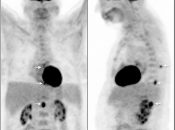

Brain Metastases:

- Far more common than primary lesions (> 10 times).

- If small and at grey-white junction, can be easily overlooked.

- Commonly from lung, breast, melanoma and GI primaries.

CNS Lymphoma:

- Usually very hypermetabolic (FDG uptake is often greater than high-grade gliomas or metastatic lesions).

- Association with immunocompromised status.